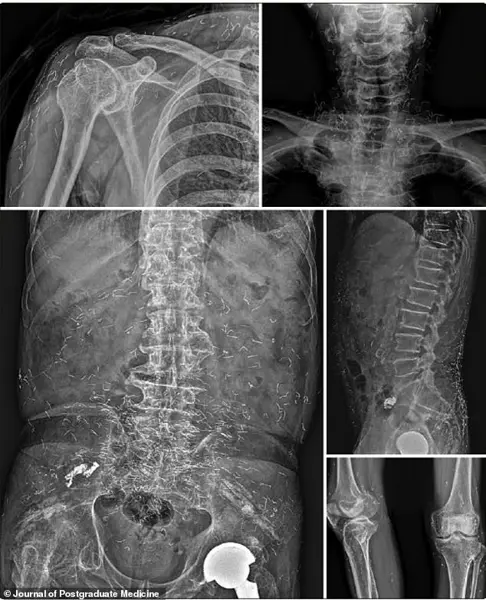

By 2022, the medical community had documented even more alarming cases.

A 73-year-old Korean man was hospitalized for a stroke.

During his evaluation, he described a 30-year history of widespread joint pain he had self-treated with gold thread acupuncture.

X-rays revealed thousands of the embedded threads throughout his body.

This revelation underscored the potential for long-term complications when such procedures are performed without medical oversight or follow-up.

In one case, a 73-year-old man who had been experiencing pain in his lower back, knees, wrists, and fingers for 30 years was finally diagnosed with rheumatoid arthritis after his stroke.

He had never been diagnosed with the condition, choosing instead to self-treat with gold thread acupuncture for years.

His symptoms only improved after he received proper medication for his newly diagnosed RA, a chronic disease where the body’s immune system attacks its own joints.